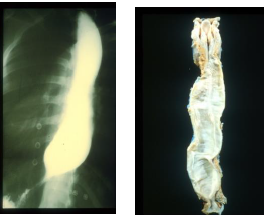

Pathology/imaging?

Meckel’s scan to look for presence of ectopic mucosa in large bowel